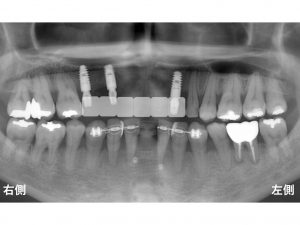

以下が初診時です。

上の前歯がグラグラしています。

上顎前歯部に残っている2歯を支えにして、

5歯分の被せ物が装着されています。

相当無理がありますよね。

以下は、インプラント手術後です。

手術時には、仮歯としてあるブリッジを一度除去して、

手術直後に戻してあります。

この状態で約3ヶ月待ちます。

インプラント手術から3ヶ月後に

上顎前歯部の2歯を抜歯します。

抜歯直後にインプラントに仮の土台をつけて

インプラントに直接仮歯を装着します。

これにより抜歯した当日に固定式の仮歯となりますので

審美的にも

食べることにも問題はありません。

ちなみに

下顎前歯部にもインプラントを予定していますが、

骨の幅が大きな問題がありましたので

骨の増大だけを行うGBR法を行ってあります。

チタンメッシュを使用したGBR法です。